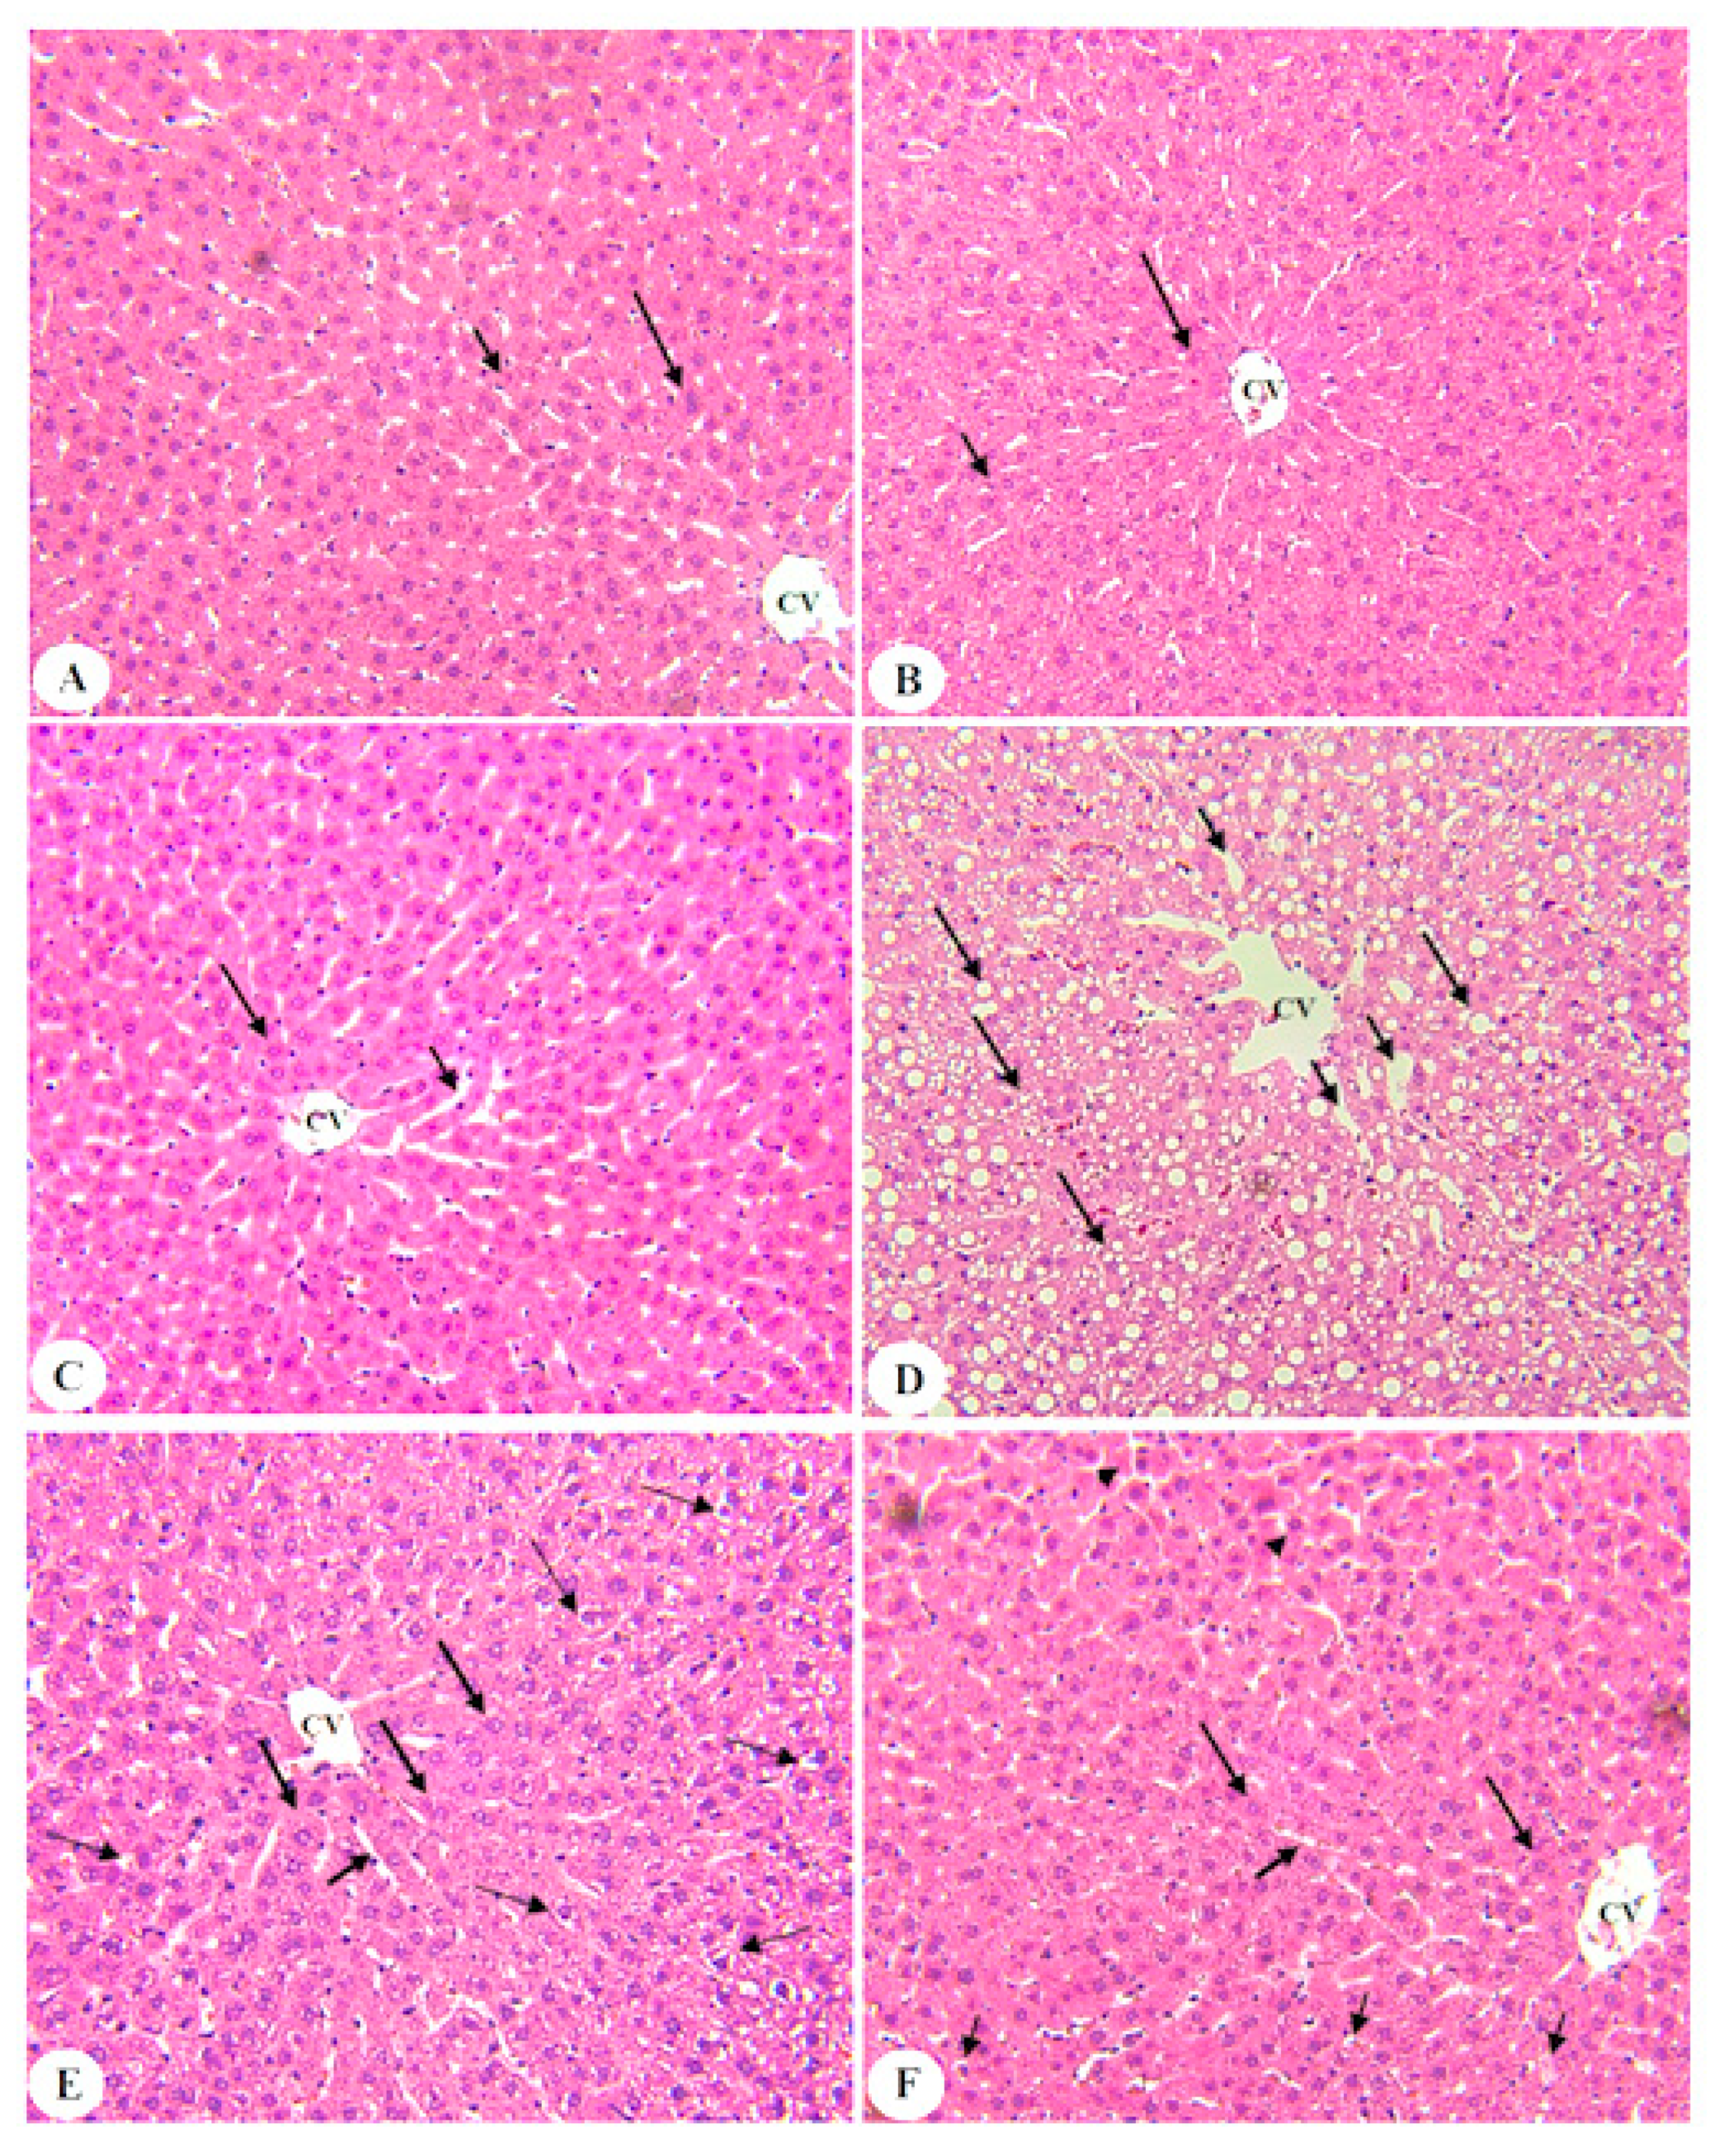

3.6. BE Improved Liver Architectures of T2DM Rats